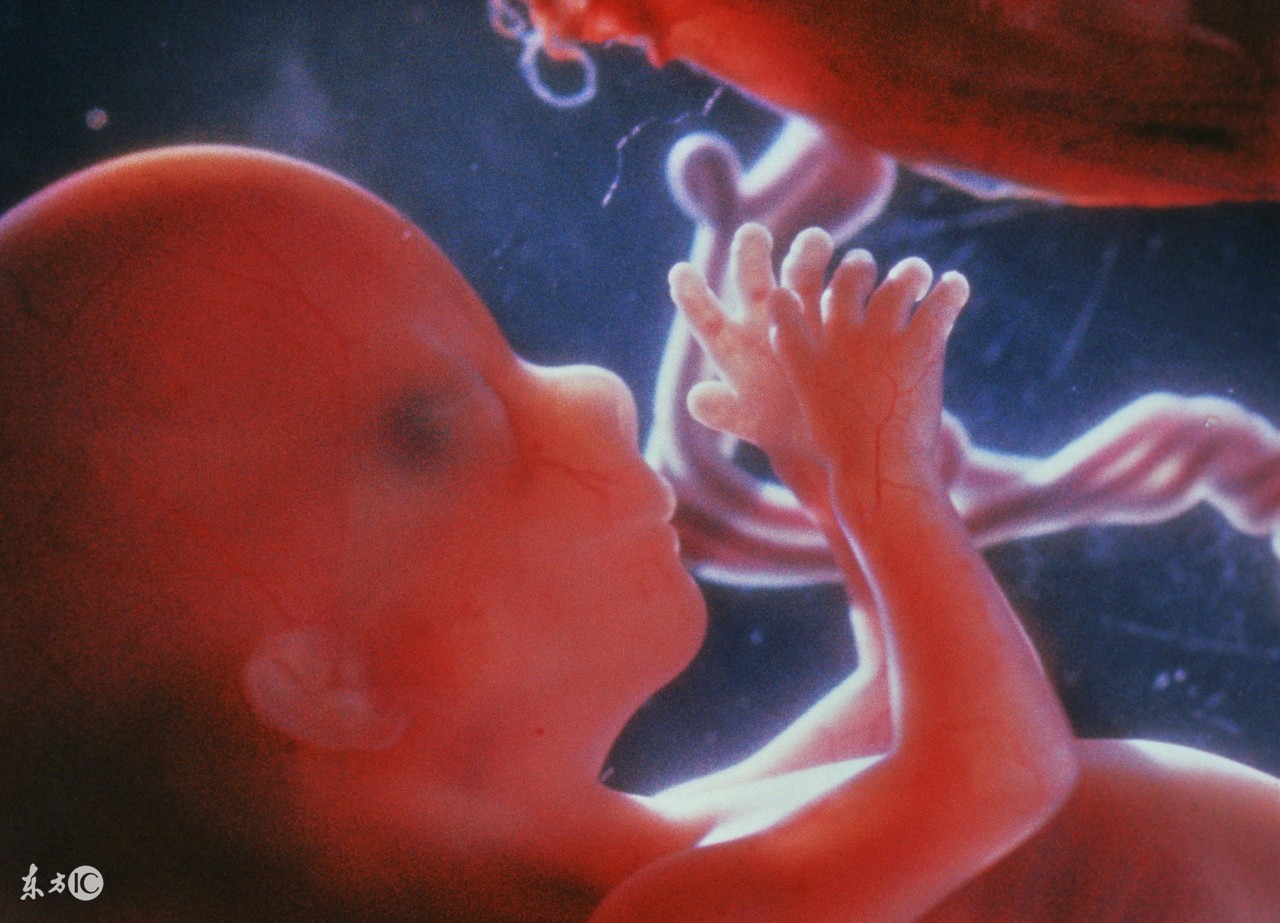

在胎儿的生长发育过程中,使胎儿能够在子宫内自如活动,因而,胎儿的肢体发育不至形成异常或畸形。

在妊娠期间,羊水能缓和腹部外来压力或冲击,保护胎儿使胎儿不至直接受到损伤。当胎宝宝在妈妈子宫里拳打脚踢的时候,也可以缓解妈妈的不适。

胎儿反复地做着吸入羊水又吐出来、吸入羊水再排出尿液的动作,可以不断地锻炼和促进肾脏功能、消化器官和肺的发育。